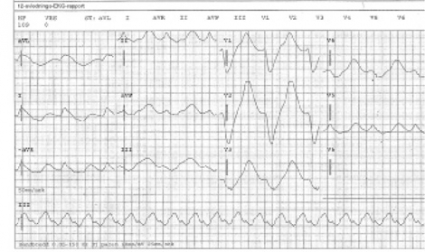

EKG. Komplettera slutligen det initiala omhändertagandet med ett diagnostiskt 12-avlednings-EKG för analys av rytm, QRS-bredd och QTc-tid. Efter denna genomgång är det ofta uppenbart om extra assistans i form av bakjour och narkosläkare behöver tillkallas för hjälp med säkring av luftväg, stabilisering och handläggning.

Breddökade QRS-komplex. Substanser som fördröjer kammardepolarisationen genom att blockera myocyternas snabba natriumkanaler (t ex tricykliska antidepressiva) kallas ofta membranstabiliserande. De ger breddökade QRS-komplex och hypotoni [22, 23]. Dessa fynd i samband med misstänkt intoxikation ska behandlas med natriumbikarbonat (NaHCO3 50 mg/ml 200 ml till vuxna; 2 mEq/kg till barn) [4, 5]. Vid utebliven effekt kan behandling med hyperventilering och hyperton koksaltlösning bli aktuell [5]. Samtidig hämning av natriumkanalerna i CNS sänker kramptröskeln. Fenytoin och fosfenytoin rekommenderas inte vid krampanfall eftersom de kan förvärra kardiotoxiciteten [4, 24]. Hyperkalemi kan orsaka liknande EKG-förändringar [25].

Förlängd QTc-tid. Substanser som blockerar hjärtmuskelcellernas kaliumkanaler inhiberar repolarisationen. Detta återspeglas av förlängd QTc-tid [22]. Tillståndet ökar risken för polymorf ventrikulär takykardi, oftast torsade de pointes. Korrigering av hypokalemi, hypomagnesemi och hypokalcemi är viktiga förebyggande åtgärder [4, 5]. Intoxikationsutlösta torsade de pointes behandlas med intravenös magnesiumsulfat [4] (1–2 g till vuxna [26]; 25–50 mg/kg till barn [27]).

Kammartakykardi. Allmänt rekommenderas lidokain (Xylocard) vid intoxikationsutlöst kammartakykardi [4, 5]. Om Xylocard inte finns tillgängligt återfinns lidokain som lokalanestesimedlet Xylocain. Ge 1 mg/kg (utan adrenalin!) intravenöst som bolus [5]. Magnesiumsulfat är andrahandsmedel men kan förvärra hypotoni [4]. Amiodaron är ett klass III-antiarytmikum som blockerar kaliumkanaler och kan förlänga QTc-tiden. Preparatets säkerhet vid intoxikationsutlösta kammartakykardier är inte fastställd. Elkonvertering har tveksam effekt vid intoxikationsutlösta arytmier och rekommenderas endast på vitalindikation [4, 5]. Vid hjärtstopp kan hjärt–lungräddning under flera timmar och även extrakorporealt stöd ha framgång [4, 5].